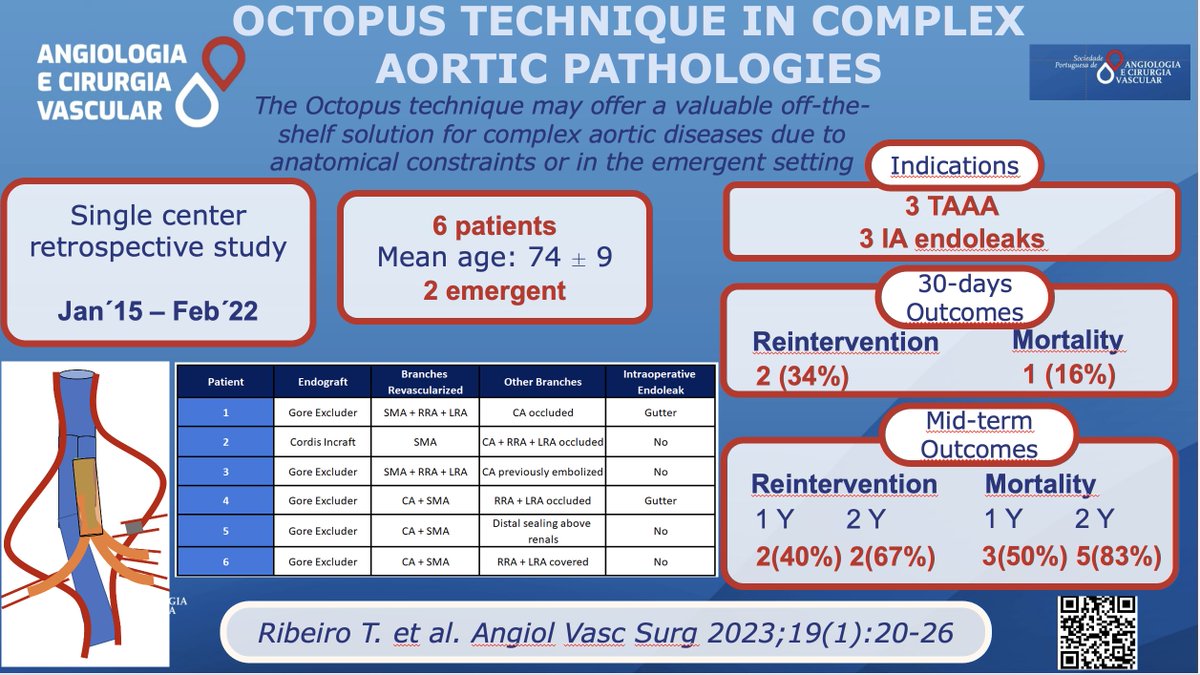

What do you think about the "Octopus Technique"? When and how do you use it? Check it out at acvjournal.com/index.php/acv/… State your opinion and personal experience below! @SPACV EJVES European Vascular Surgeons in Training (EVST) ESVS Society for Vascular Surgery